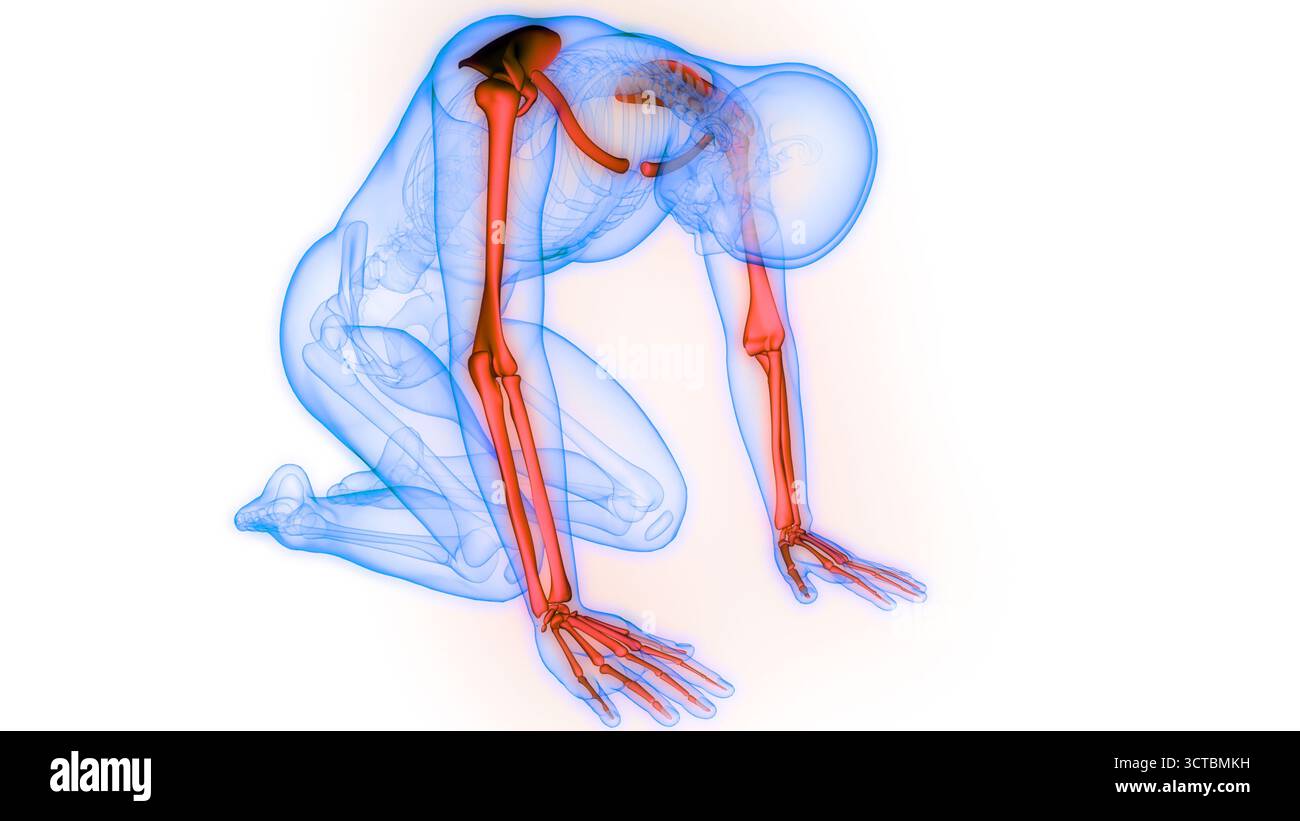

RF2JNYJM7–Präzise Knochen des Arms oder der oberen Extremität des menschlichen Skelettsystems oder Skeletts isoliert auf weißem Hintergrund 3D Rendering Illustration. Anterior und

RF2JNYJM8–Genaue vordere oder vordere Ansicht der Knochen des Arms oder der oberen Extremitäten des menschlichen Skelettsystems isoliert auf weißem Hintergrund 3D Rendering Illustration. Ein

RF2JNYJJK–Genaue 3-Viertel-Vorderansicht oder Vorderansicht der Arm- oder oberen Extremitätenknochen des menschlichen Skelettsystems isoliert auf weißem Hintergrund 3D Rendering il